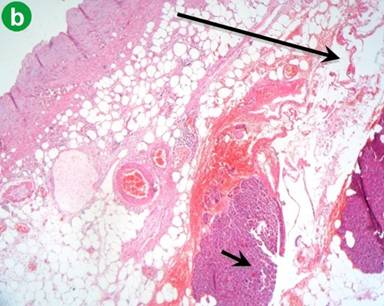

Macroscopically, the mass had a cystic and lobulated appearance (Figure 4). The microscopic findings of the mass are shown in Figure 5. Furthermore, the diagnosis of a cystic lymphangioma of the pancreas was confirmed by immunohistochemistry which showed CD3 and factor VIII positivity for cells lining the dilated channels in a sample of the head of the pancreas.

|

Figure 5 a. Aggregates of lymphoid cells (short arrow) adjacent to closely packed lymphatic channels (long arrow). (H&E staining; low power magnification: x10). b. Pancreatic tissue (short arrow) and lymphatic channels (long arrow). The background is formed by mesodermal tissue. (H&E staining; low power magnification: x10). |